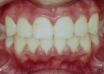

case dot 改善前牙錯咬